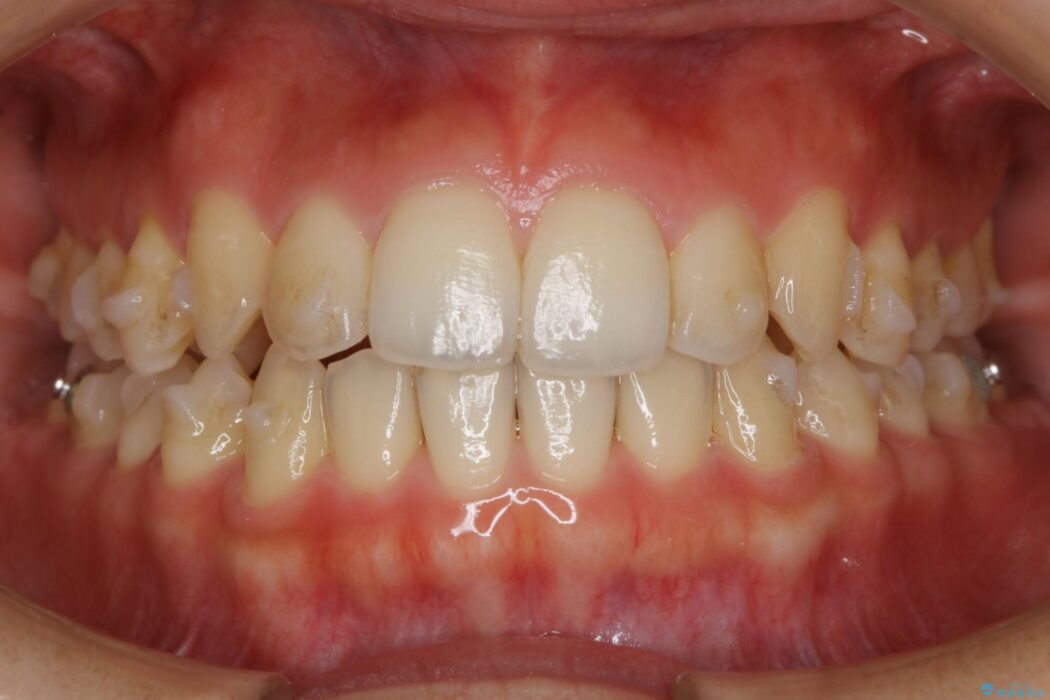

- 患者様:20代女性

- 治療期間:11ヶ月

- 矯正装置:インビザライン ライトパッケージ

- 概算治療費:44万円(紹介10%割引)

※費用は治療当時の料金となります - 担当医:福本健生

治療後写真を見ても歪みが解消され、歯列弓がきれいに整ったのが分かると思います。インビザラインをしっかりと装着されていたこともあり、矯正としては短期間の治療となりました。